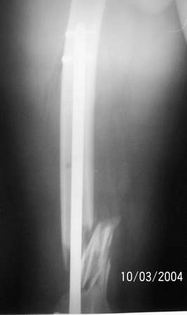

A 34 year old male was injured in a car accident.

The femur injury was treated by long retrograde interlocking nail.

I would expect healing though alignment could have been better if Poller screw or temporary wire was used.